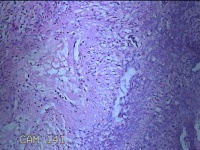

阑尾

临床诊断

急性坏疽性阑尾炎 弥漫性腹膜炎

一般病史

转移性右下腹疼痛3天。

标本名称

大体所见

灰白暗红色阑尾2.5x0.8x0.3cm一条,表面糜烂,肿胀,带大量系膜,部分已切开,见腔内暗红色,另有灰褐色粪石1.9x0.7x0.3m一枚。